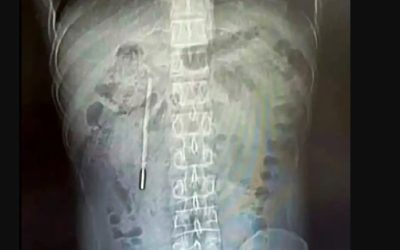

Termometru înghițit de un copil chinez: Medicii, uimiți de ceea ce au găsit

Un bărbat din China a descoperit, după 20 de ani, cauza durerilor sale abdominale persistente: un termometru cu mercur înghițit în copilărie, aflat acum...